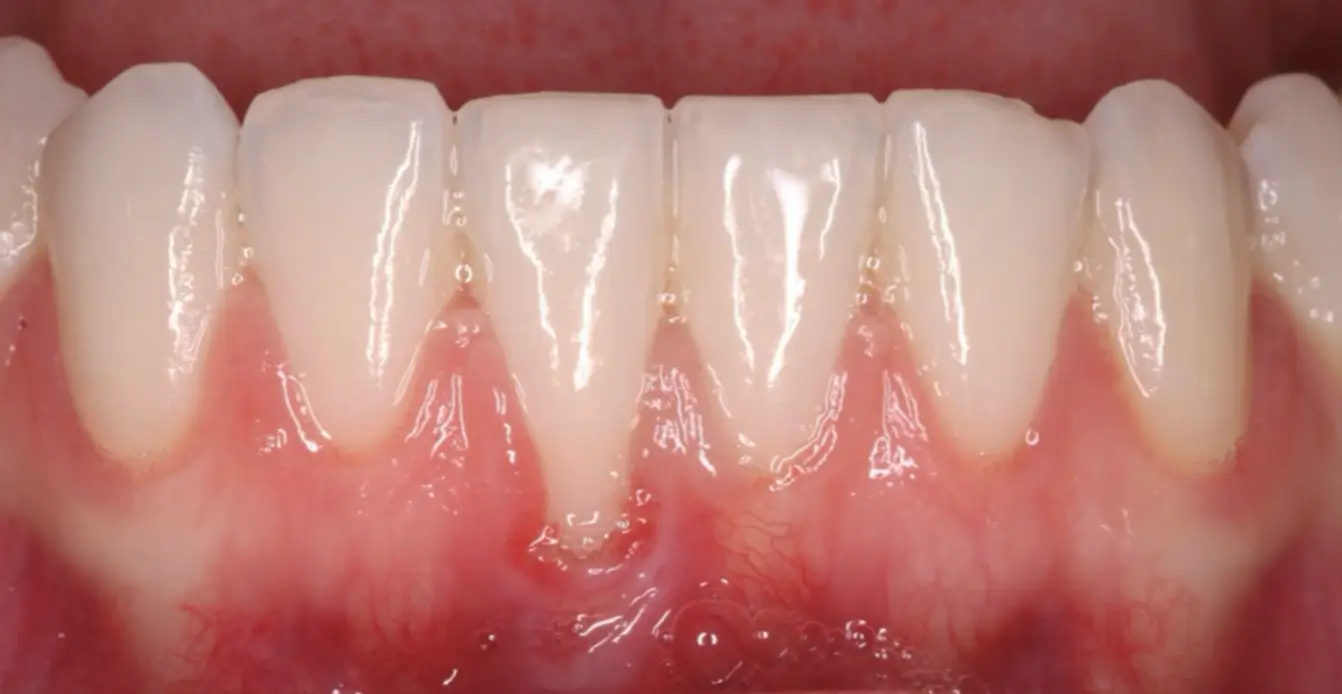

Frenectomy

before

after